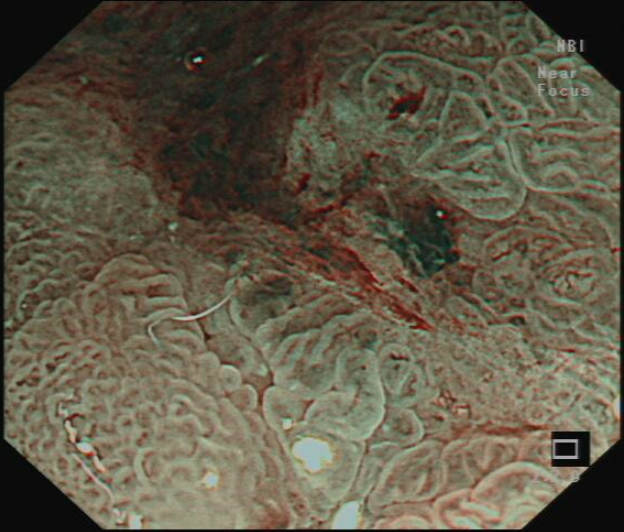

图3术中内镜剥离病变后的创面

ESD术前进行内镜精查发现病变胃镜白光下,NBI放大观察及靛胭脂染色,病变均符合内镜下胃早癌表现。胃角病变是ESD操作最困难部位,随着充气的增多,镜身会远离胃角,不容易接近病变,增加了剥离难度,术中又发现病变中央存在纤维化粘连,为手术剥离增加了风险,唐印华教授凭借精湛的技术和丰富的腔镜经验,利用牙线—钛夹牵引,增加了黏膜下层的空间,使黏膜下视野充分暴露,且镜身更容易接近病变,大大提高了剥离的速度,使手术快速顺利结束。